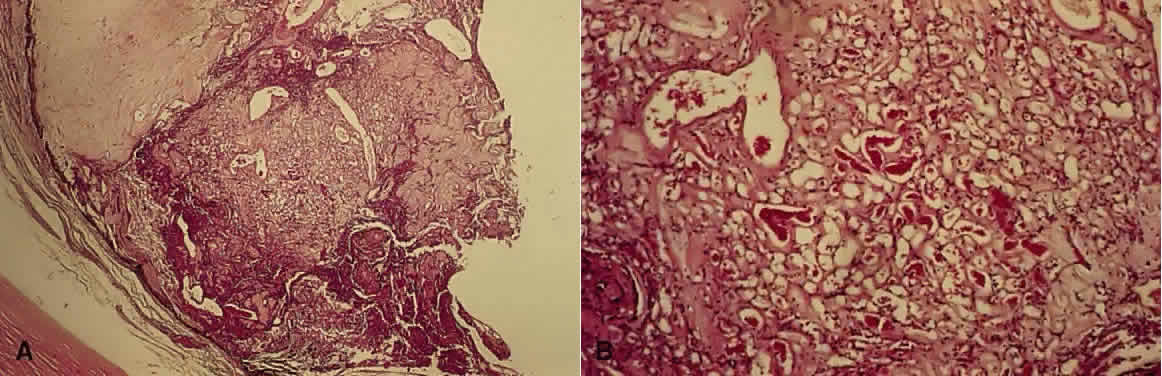

The characteristic retinal lesion in this disease is a capillary hemangioma (hemangioblastoma), composed of blast-like vascular endothelial cells and pericytes, along with foamy cells that contain lipid (Figs. 3 and 4).26,27 The origin of these foamy cells has been controversial.28 Recent work has shown that they are the true neoplastic component of the hemangioblastoma. Von Hippel-Lindau angiomatosis is inherited as an autosomal dominant with incomplete penetrance. The mode of inheritance and the mechanism of disease are similar to those of retinoblastoma—that is, the condition is inherited as an autosomal dominant trait, so that the patient is heterozygous for the abnormal gene. However, at the cellular level, within the tumor, the neoplastic cells undergo a second mutation and are homozygous. These homozygous cells are the tumor cells, and they express vascular endothelial growth factor.29

Fig. 3. Angiomatosis of the retina. A. Fundus picture of retinal angioma in a 16-year-old patient. B. Hemangioblastoma (capillary hemangioma) replaces the full thickness of the retina. C. High magnification shows capillary blood-filled spaces intimately associated with characteristic pale, foamy, polygonal stromal (astrocytic) cells.(A, fundus picture [SEI 79-21]; B, H&E, × 40 [SEI 73–207]; C, H&E, × 252 [SEI 73–209]. Courtesy of Dr. DH Nicholson).

Fig. 4. Retinal hemangioblastoma. A. Low-power view shows a hemangioblastoma at the ora serrata with disruption of normal architecture. The ciliary epithelium has proliferated beneath the hemangioblastoma (H&E, × 7.8). B. Higher-power view shows the vascular channels (H&E, × 31).

Large feeder vessels supply and drain the hemangioblastoma, which is typically located inferotemporally near the equator. The small vessels within the tumor leak lipid-rich fluid, which can result in retinal exudates and hemorrhages. By electron microscopy, the tumor vessels have fenestrations, making them permeable to these metabolites.30 Secondary complications include exudative retinal detachment and fibroglial bands. Also, neovascularization of the iris, peripheral anterior synechiae, and secondary angle-closure glaucoma may result.